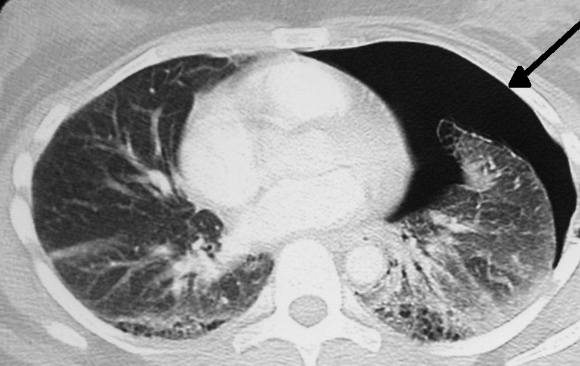

기흉이 심해지면 흉막강 내 공기가 계속 축적되어 폐와 심장을 압박하는 긴장성 기흉이 발생할 수 있는데, 이 상태는 생명을 위협하는 응급상황으로 혈압 저하, 청색증, 의식 저하 등이 나타나며 즉각적인 응급조치가 필요합니다. 진단 방법은 보통 흉부 X선 촬영으로, 허탈된 폐와 흉막강 내 공기를 확인하며, 더 정밀한 원인 분석과 확진을 위해 흉부 CT를 시행하기도 합니다. 청진 시에는 기흉이 있는 쪽 가슴에서 호흡음이 감소하거나 사라진 점도 진단에 도움이 됩니다.